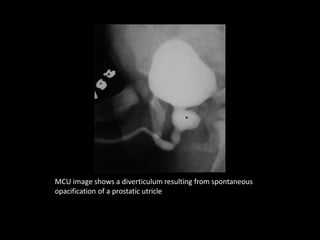

MCU image shows a diverticulum resulting from spontaneous

opacification of a prostatic utricle